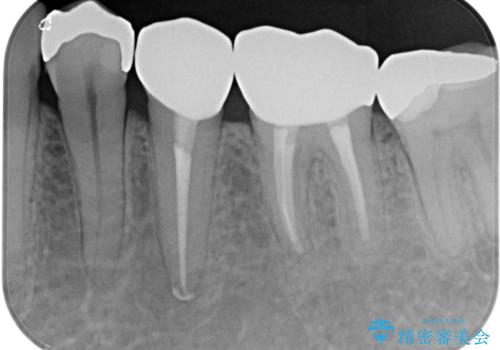

大臼歯の治療後に海外赴任され、数年ぶりに帰国されました。

奥歯に痛みがあるとのことで診察を行ったところ、海外(アメリカ)にて処置をした手前の歯が既に失活していることが分かりました。なお、治療を行った大臼歯はレントゲン写真上の治癒が認められました。

症状のあった歯に対しても根管治療を行い、同様に補綴治療を行いました。